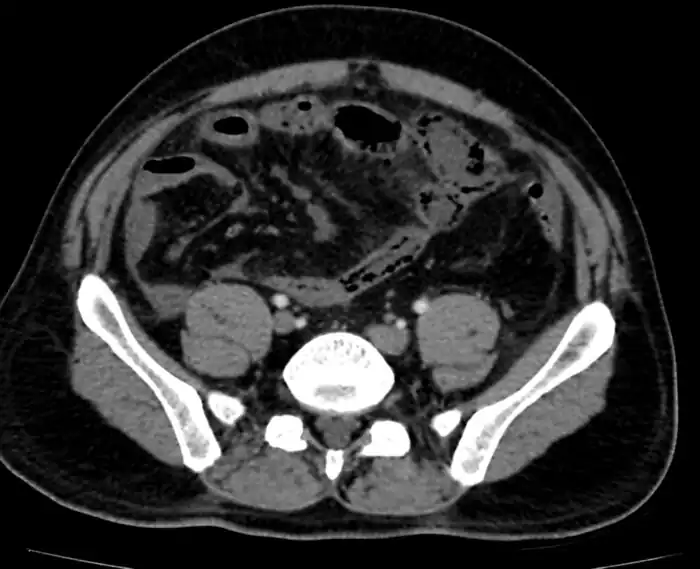

Mesenteric ischemia/CT image

Mesenteric ischemia